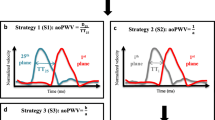

Phase contrast MRI

Phase contrast MRI acquisitions were specifically designed to acquire time-velocity curves at two slices locations (aortic arch and descending aorta approximately 10 cm apart) to estimate transit time (ΔT) as shown in Fig. 1. Subjects were scanned using a Philips Achieva 3 Tesla scanner and a six channel cardiac coil was employed for signal reception. Phase contrast MRI data was acquired by experienced radiographers using a high temporal resolution sequence (repetition time / echo time / flip angle / number of excitations / slice thickness = 5 ms/2.9 ms/100/1/8 mm, SENSE factor 2, field of view 300 mm × 225 mm, reconstructed voxel size 1.17 mm2, velocity encoding = 150 m/s, 44 phases, breath hold duration ~19 s) at both slice locations which were the aortic arch (AAo) and the descending (DAo) aorta (Fig. 1). Additional scout images were acquired to facilitate positioning of the phase contrast MR acquisitions and to ensure that the slices were positioned perpendicular to aorta at both locations. Q-flow analysis package (Philips, Viewform) was employed to extract time-velocity curves as shown in Fig. 1 and to estimate precise distance (ΔX) between the two slice locations. The time-velocity curves were then used to determine transit time (ΔT) and compute MR pulse wave velocity = ΔX/ΔT using an in house Matlab based program. A reproducibility analysis of this technique was performed in seven normal volunteers, repeating scans at two sessions, and within each session performing the scanning twice. For session one the values were 4.9 ± 1.6 and 4.5 ± 1.6 m/s (mean difference 0.4 ± 0.9) and session two 5.5 ± 1.6 and 5.2 ± 1.2 m/s (mean difference 0.3 ± 0.7).

Illustration of Vicorder and phase contrast MRI techniques. In panel a, examples of simultaneous Vicorder carotid and femoral arterial waveforms are shown. Panel b shows the two slices of thoracic aorta (AAo – aortic arch, and DAo descending aorta) between which distance is measured (ΔX), and in panel c phase contrast MRI flow images showing ΔT which is the time delay between of the initial upstroke in flow between the two slices